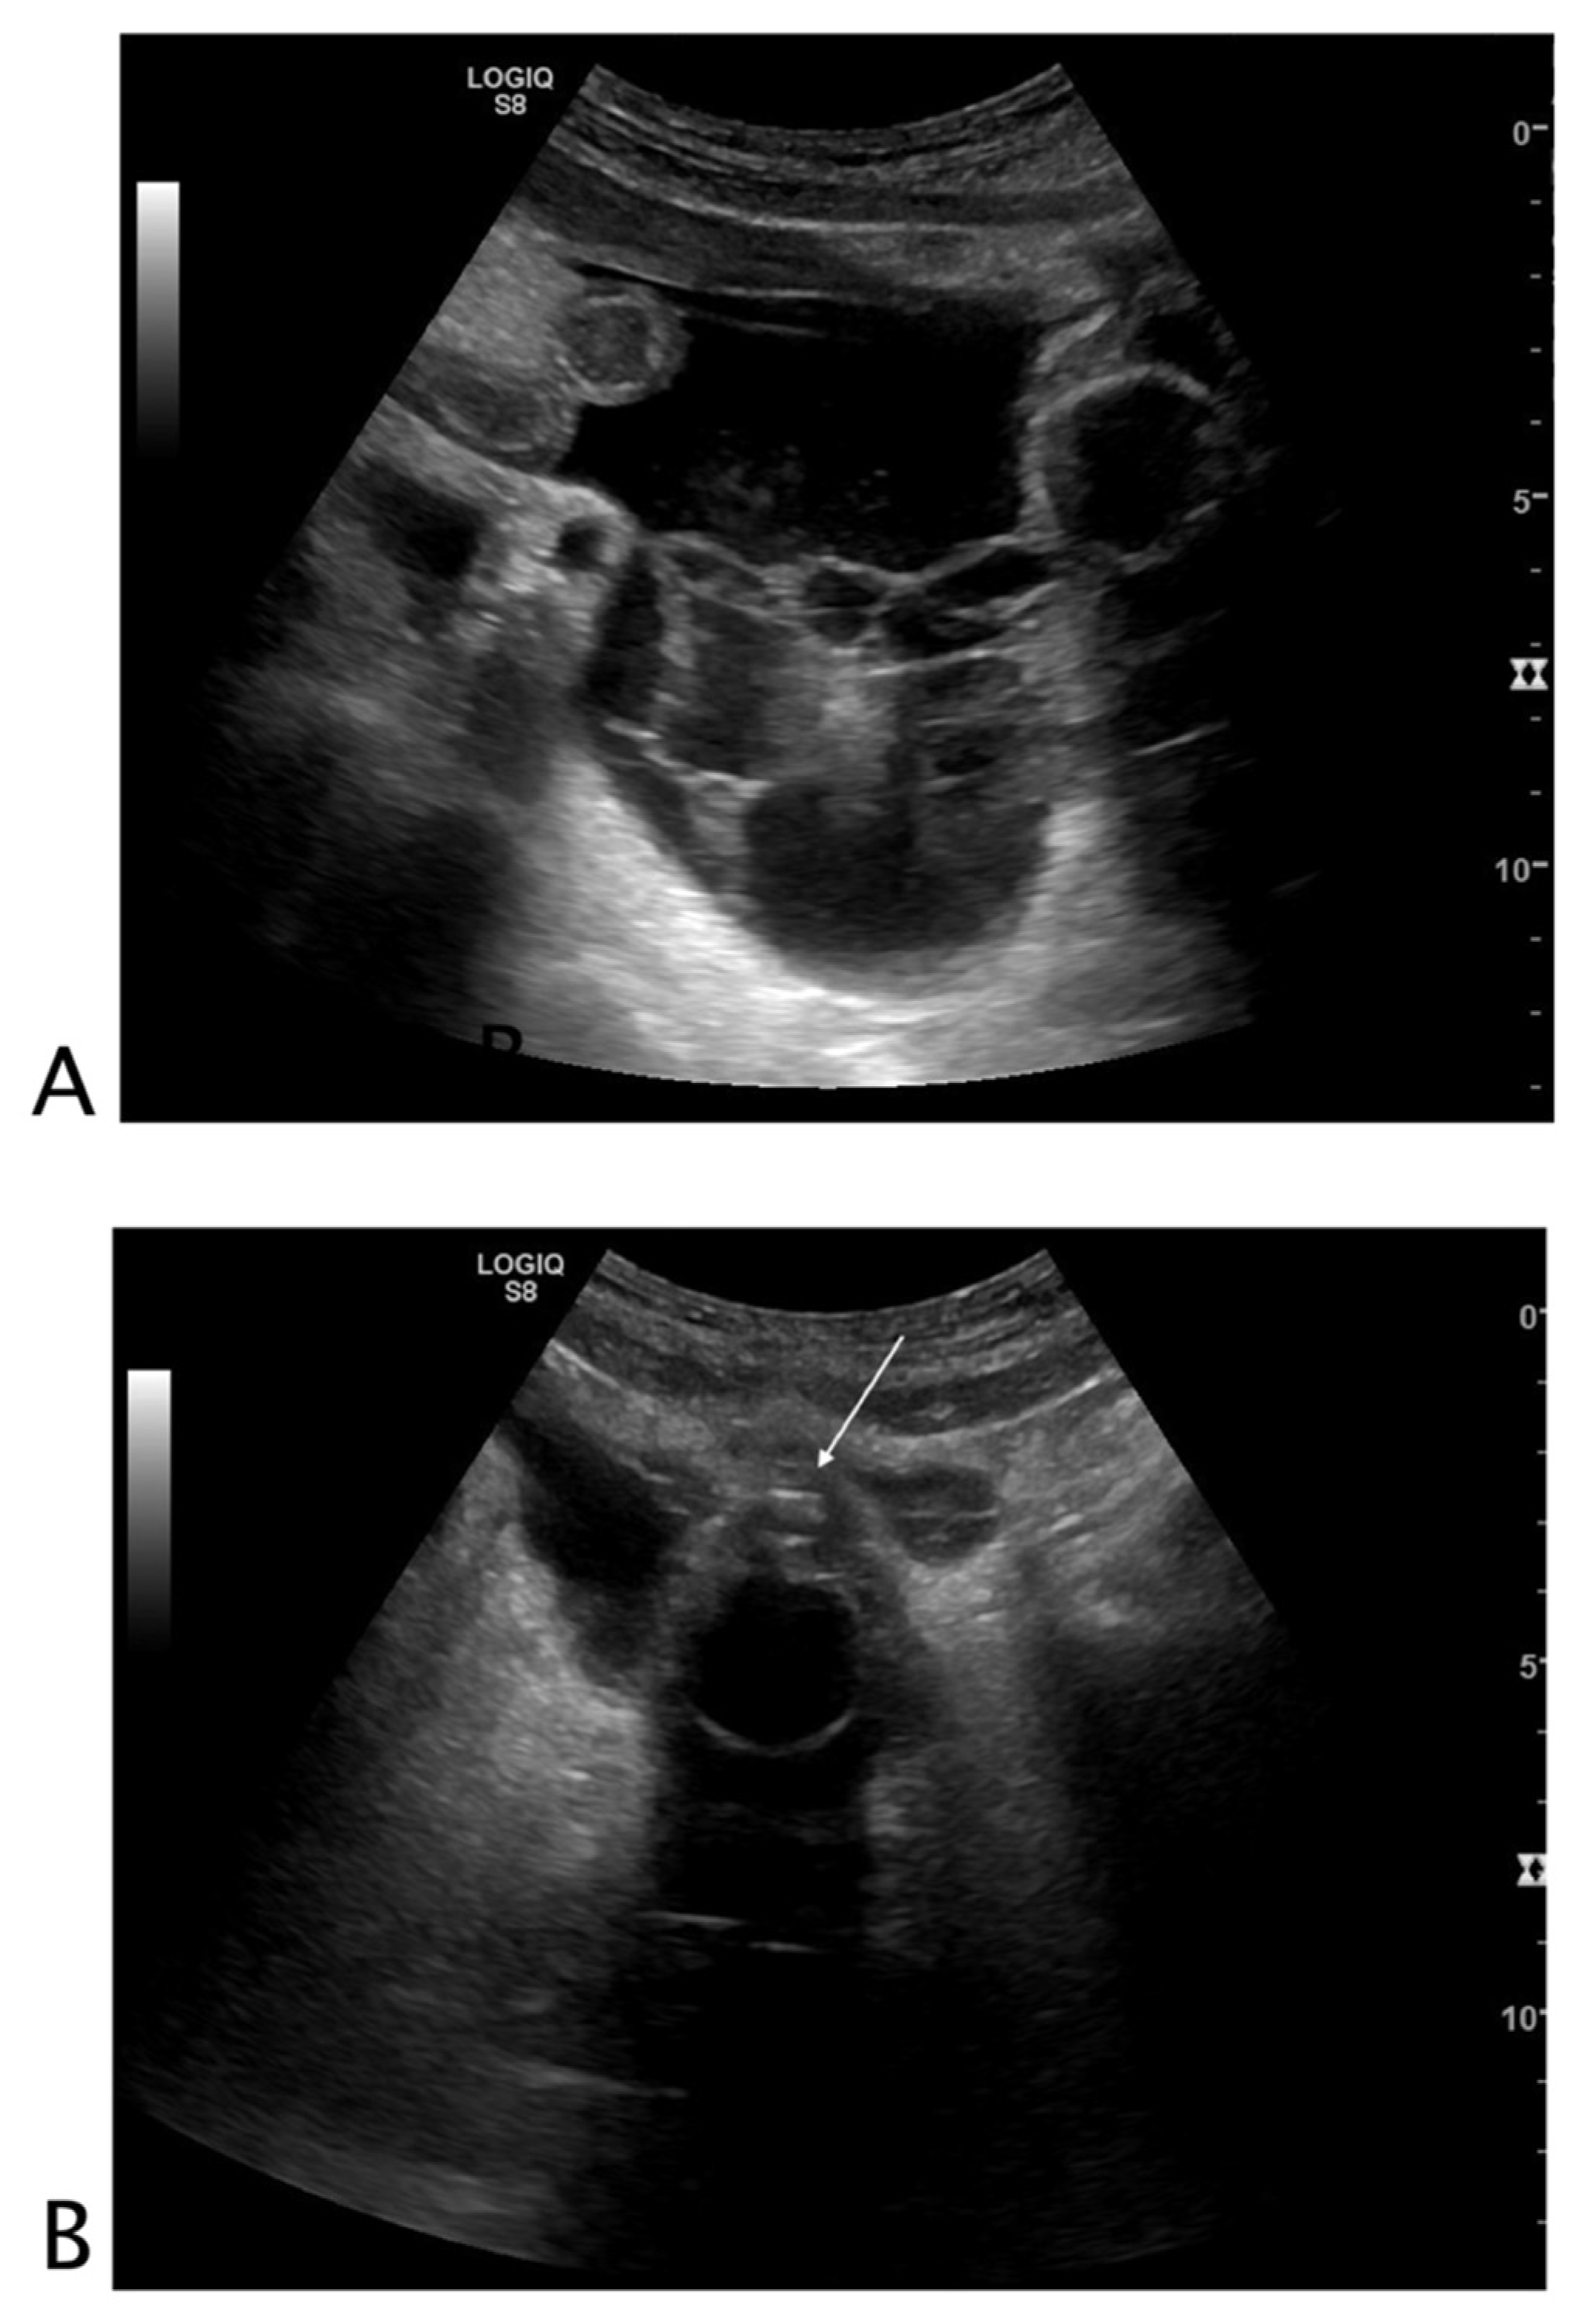

2.3. Looking for Black That Is Not Clearly Black

2.3.1. Vessels

2.3.2. Urinary Tract

2.3.3. Biliary Tract